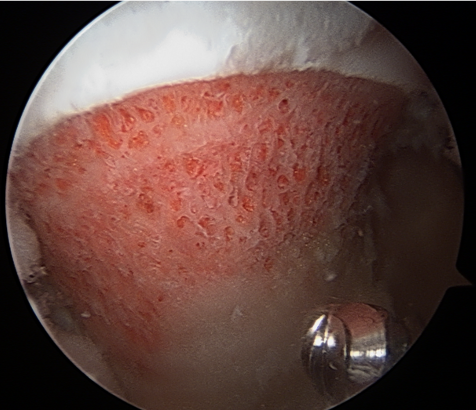

Assess for Labral Tears

Expose acetabulum

- use cautery to expose acetabulum while not injuring labrum